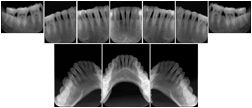

3. A dental provider wishes to capture a series of DICOM IO images for the patient’s dentition. The tooth morphology, teeth are divided into molars, premolars, canines and incisors, and a number of images for each jaw. The anatomic information was captured utilizing the triplet of schema. This standard code sequence is based on ISO 3950-2010, Dentistry - Designation system for teeth and areas of the oral cavity.

In most standard cases, images are oriented in structured layouts. These structured displays are useful to be shared between providers for reference purposes.

Table OO.1.1-1 shows structured display standard templates, where Viewset ID is based on the Japanese Society for Oral and Maxillofacial Radiology (JSOMR) classification provided by JIRA (Japan Medical Imaging and Radiological Systems Industries Association, www.jira-net.or.jp). Expected or typical teeth to be imaged location, region and designation codes are based on ISO 3950-2010, Dentistry - Designation system for teeth and areas of the oral cavity. For all the hanging protocols listed in OO.1.1-1, the value to use for Hanging Protocol Creator (0072,0008) is "JSOMR" and the value to use for Hanging Protocol Name (0072,0002) does not include "JSOMR" (e.g., "DL-S001A", not "JSOMR DL-S001A").